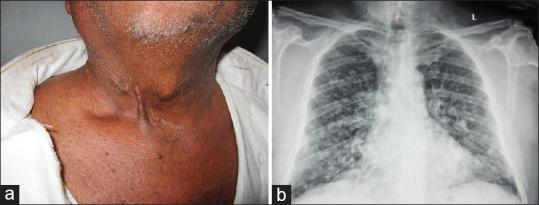

Ulcerative cutaneous nodule as a presenting feature of recurrent thyroid carcinoma.

Indian J Dermatol. 2014 Nov;59(6):616-8. doi: 10.4103/0019-5154.143545.